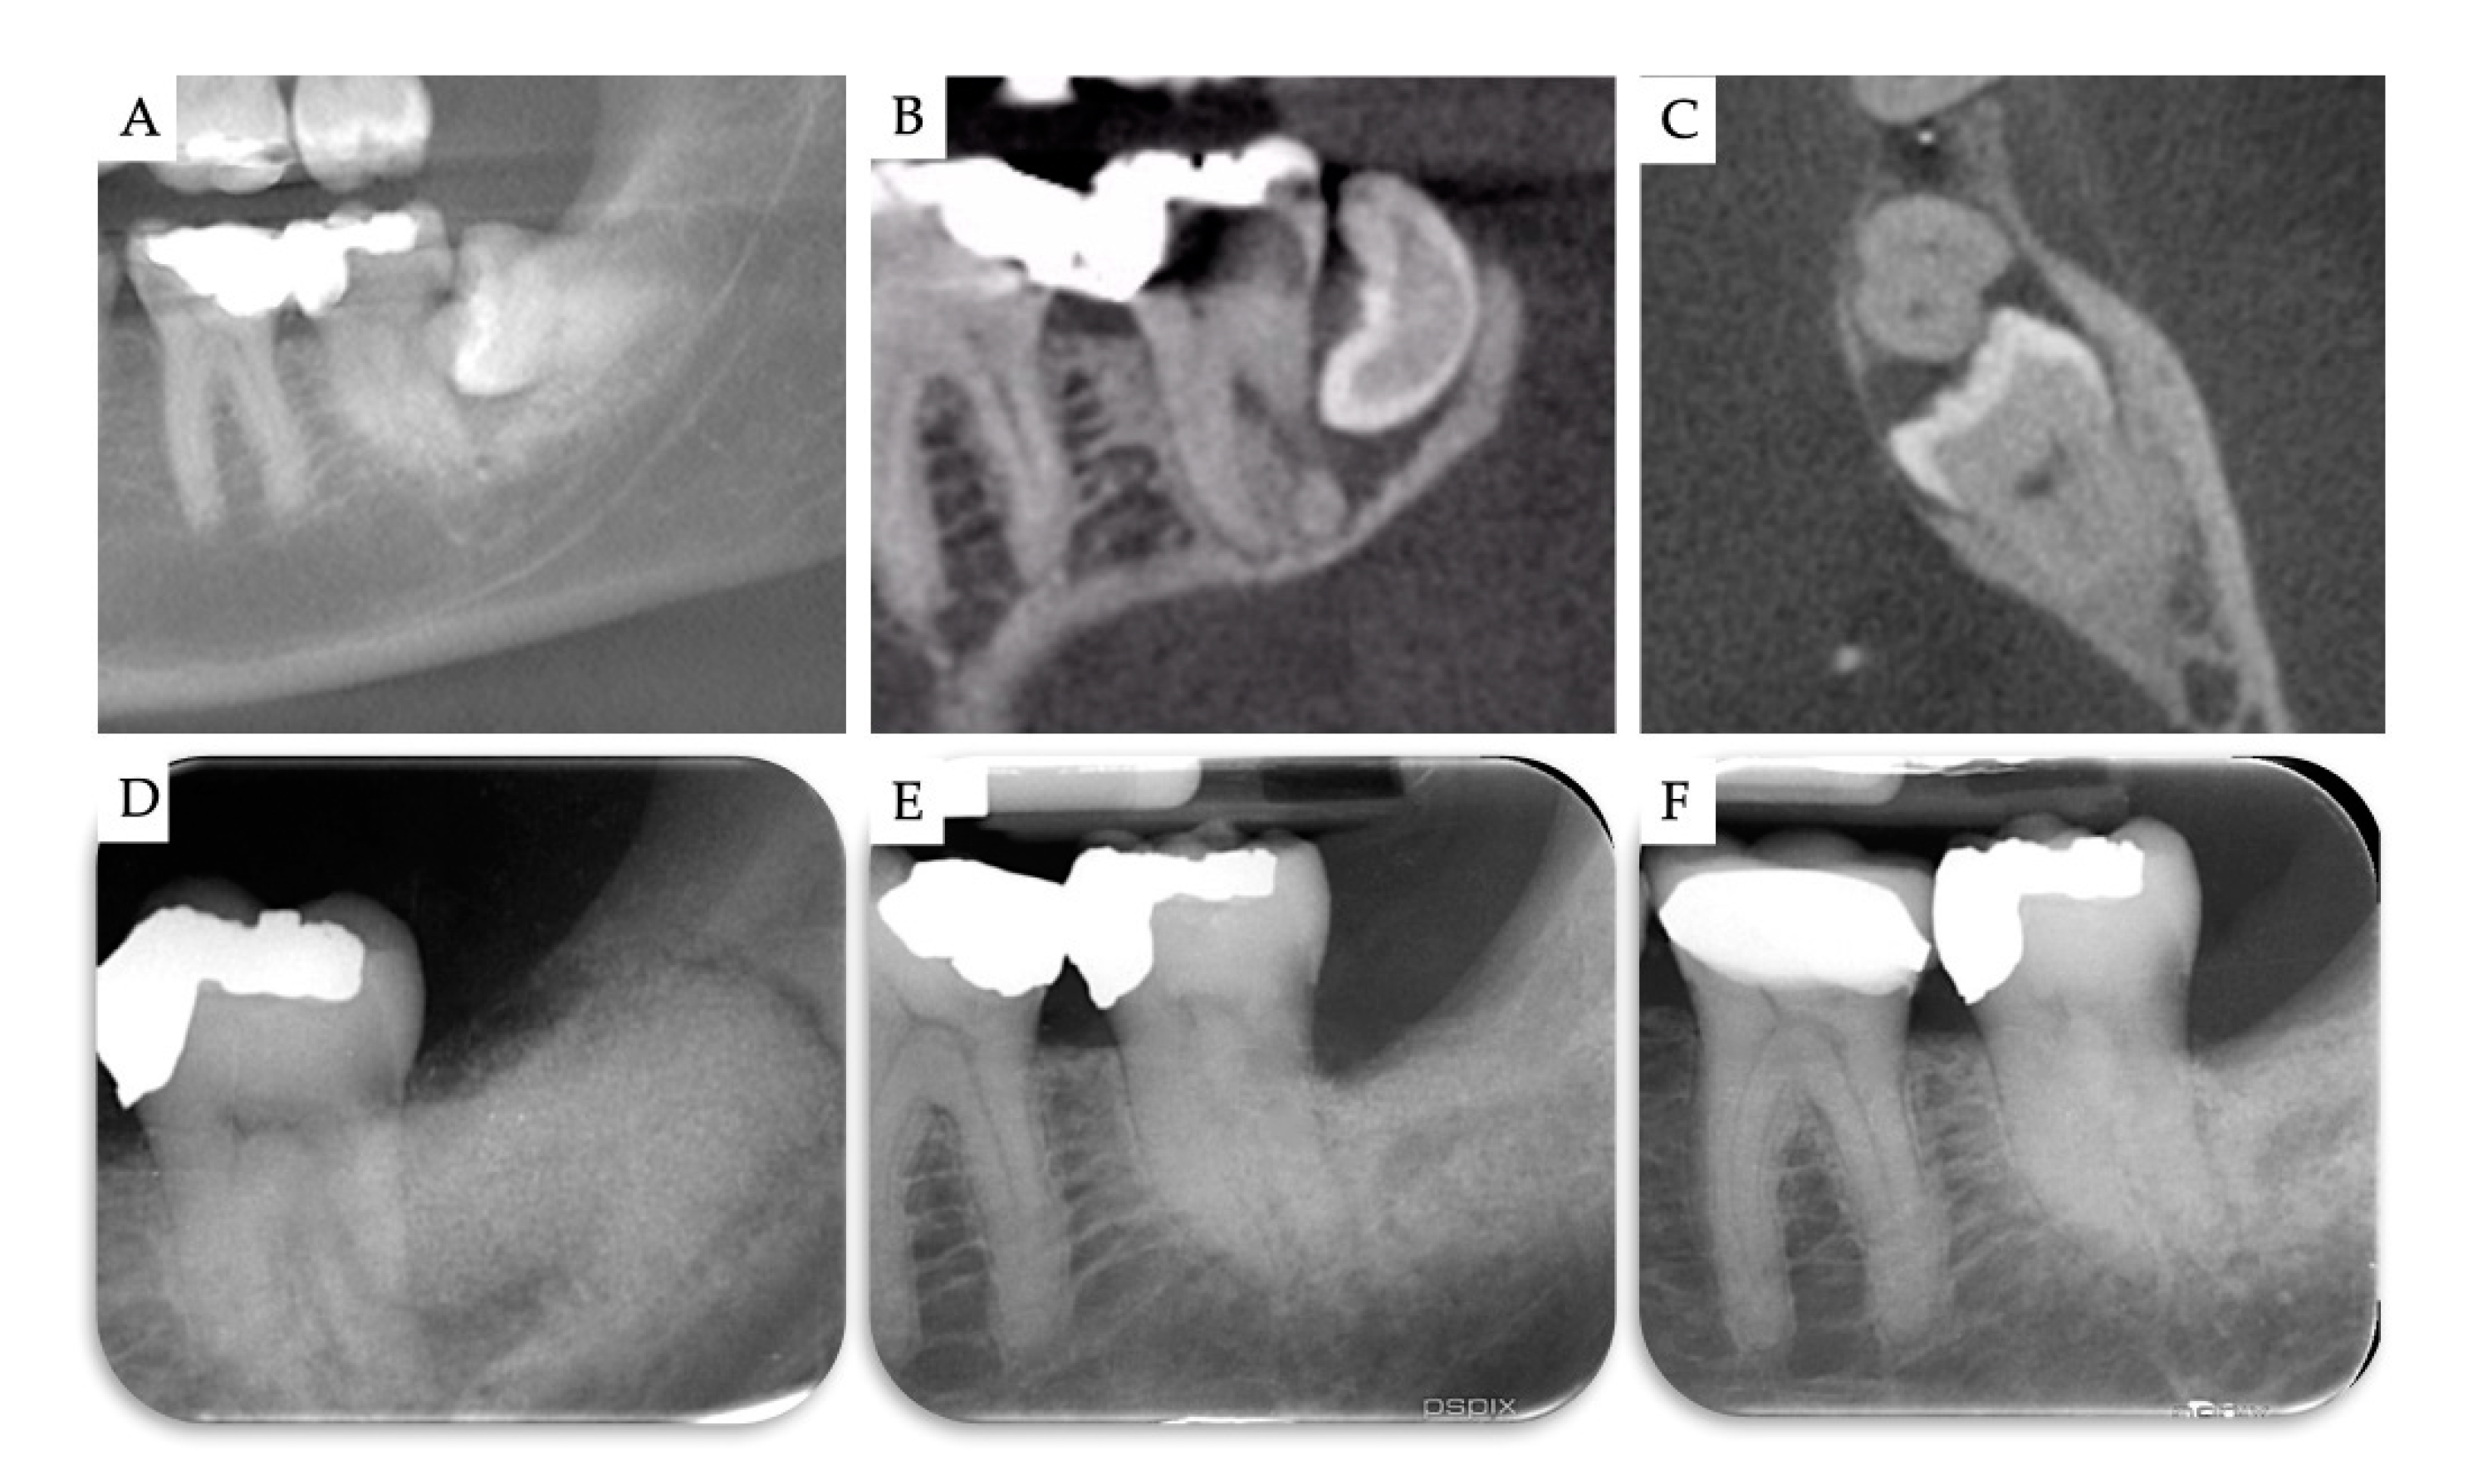

3. Results

| Case | Gender | Age | Smoker | M3 | Impaction | Follow-Up (years) | PD T0 (mm) | PD T1 (mm) | BD T0 (mm) | BD T1 (mm) | BG (mm) |

|---|---|---|---|---|---|---|---|---|---|---|---|

| 1 | F | 51 | No | 48 | Mesio-angular | 2 | 12 | 3 | 11.1 | 5.2 | 5.86 |

| 2 | F | 36 | No | 38 | Horizontal | 2 | - | 1 | 7.4 | 1.3 | 6.1 |

| 3 | M | 42 | No | 38 | Horizontal | 1 | - | 2 | 10.2 | 4.4 | 5.79 |

| 4 | M | 34 | No | 48 | Horizontal | 1 | - | 2 | 8.6 | 2.1 | 6.51 |

| Mean | 40.75 | 1.5 | 2.00 | 9.33 | 3.25 | 6.07 | |||||

| SD | 6.61 | 0.5 | 0.71 | 1.43 | 1.6 | 0.28 |